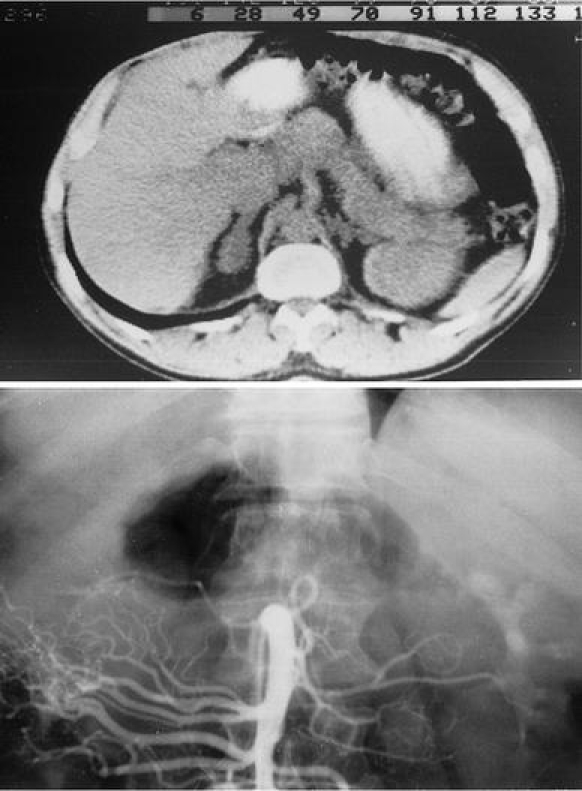

Case 1. A 50-year-old male was referred in 1982 because of recurrent kidney stones, hypercalciuria (24 h urinary calcium excretion between 14.5 mmol and 16.3 mmol, normal upper value 6 mmol/24 h) and hypercalcaemia (serum Ca between 2.86 mmol/l and 2.95 mmol/l, normal values between 2.25 mmol/l and 2.60 mmol/l). The referring internist suspected the patient of having mild acromegaly, because of the coarse facial features. The diagnosis primary hyperparathyroidism was confirmed and the patient underwent parathyroid surgery, and two large adenomas were removed, after which the patient became normocalcaemic until now. The patient had noted increase in size of his feet and hands since several years, but otherwise he had no complaints. Glucose loading decreased GH from 12 mU/l to below 0.5 mU/l (normal value during glucose suppression is below 2.5 mU/l with RIA). Intravenous administration of 200 μg TRH, however, increased GH from 3.5 mU/l to 58.0 mU/l and PRL increased from 7.0 μg/l to 13 μg/l. CT scanning of the pituitary gland with the first generation CT-scanner (in 1983) did not show abnormalities, and CT scanning of the thorax and abdomen also failed to show the presence of a tumor. Because of progressive complaints of fatigue after cure for hyperparathyroidism and strong clinical suspicion of acromegaly, the patient underwent transsphenoidal pituitary exploration. At surgery a small suspect lesion was removed with part of the surrounding pituitary gland tissue. Histology of the lesion was compatible with somatotrope hyperplasia. After the patient had recovered from surgery, CT, MRI and arteriographic studies were repeated, and serum samples were sent to St. Bartholomew’s Hospital, London, UK (Dr L.H. Rees) for GHRH measurement. The abdominal CT-scan showed a 4 cm mass in the middle section of the pancreas (Fig. 1) and the mass was also visible with selective arteriography of the superior mesenterial artery (Fig. 1). The fasting GHRH concentration amounted to 3,810 pg/ml (normal range 10–60 pg/ml). GHRH concentration in the arterial supply to the tumor was 12,470 pg/ml, and in the venous tumor outflow 31,120 pg/ml, while in the systemic venous system the concentration was 8,900 pg/ml. After removal of the pancreatic tumor, peripheral GHRH concentration decreased to normal values of 16–33 pg/ml. In retrospect, the first abdominal CT-scan, 2 years before, already showed the pancreatic tumor with a similar size.

Fig. 1.

Upper panel shows the abdominal CT at the level of the pancreas and the lower panel the selective arteriography of the superior mesenterial artery